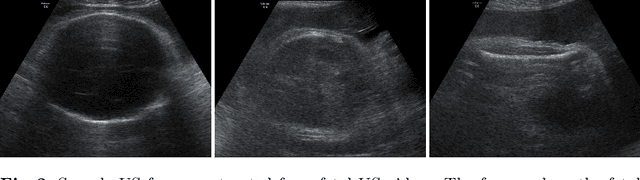

Abstract:Predicting fetal weight at birth is an important aspect of perinatal care, particularly in the context of antenatal management, which includes the planned timing and the mode of delivery. Accurate prediction of weight using prenatal ultrasound is challenging as it requires images of specific fetal body parts during advanced pregnancy which is difficult to capture due to poor quality of images caused by the lack of amniotic fluid. As a consequence, predictions which rely on standard methods often suffer from significant errors. In this paper we propose the Residual Transformer Module which extends a 3D ResNet-based network for analysis of 2D+t spatio-temporal ultrasound video scans. Our end-to-end method, called BabyNet, automatically predicts fetal birth weight based on fetal ultrasound video scans. We evaluate BabyNet using a dedicated clinical set comprising 225 2D fetal ultrasound videos of pregnancies from 75 patients performed one day prior to delivery. Experimental results show that BabyNet outperforms several state-of-the-art methods and estimates the weight at birth with accuracy comparable to human experts. Furthermore, combining estimates provided by human experts with those computed by BabyNet yields the best results, outperforming either of other methods by a significant margin. The source code of BabyNet is available at https://github.com/SanoScience/BabyNet.